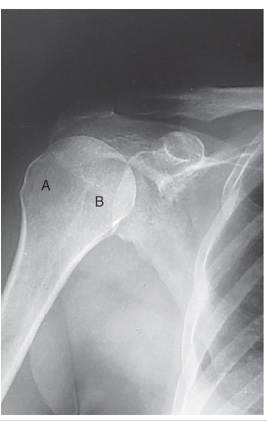

head of humerus

A

greater tubercle

B

coracoid process

glenoid fossa

C

acromion process

D

lesser tubercle

E

humeral head

F